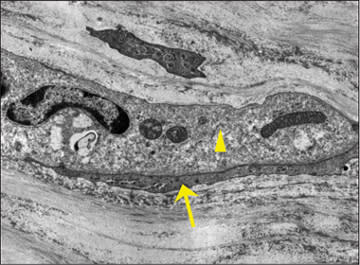

The actual removal of the entire ALL corneal layer is accomplished with the aid of cells recruited from areas beyond the cornea (Figure 3) (Mathew et al, 2009). What these cells are, where they come from and what exactly they are doing is the focus for future studies in our laboratory.

Figure 3. Transmission electron micrograph of a non-corneal cell (triangle) in the anterior stroma. This undocumented corneal visitor has an intimate relationship with a keratocyte (arrow).